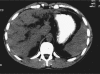

Background: Caroli's disease (CD) is a benign congenital disorder characterized by segmental cystic dilatation of the intrahepatic biliary ducts. Therapeutic strategy includes medical treatment, percutaneous, endoscopic or surgical drainage of the affected bile ducts, liver resection or transplantation. The aim of this study was to analyse the results and long-term follow-up of a consecutive series of patients who underwent surgical treatment for CD.

Results: The average age of the patients was 45.8 years. Recurrent cholangitis was the main clinical manifestation (70%). In unilateral CD a liver resection was performed in nine patients (left lateral sectionectomy in seven, left hepatectomy in one and right hepatectomy in one). In bilateral disease a cholecystectomy, duct exploration, hepaticojejunostomy and liver biopsy of both lobes were performed. Average follow-up was 60 months. All the patients are alive and free of symptoms without recurrence in the remnant liver.